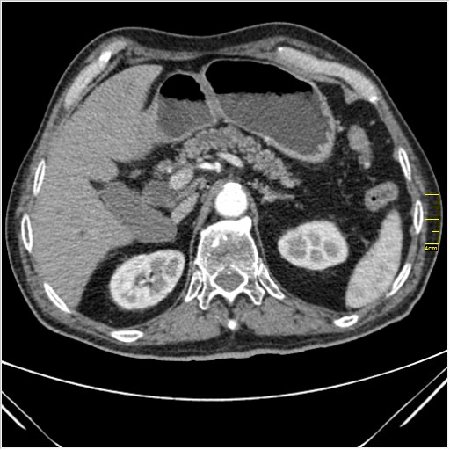

Мужчина 62 года с желтухой

Опухоль головки поджелудочной железы, расширение холедоха и панкреат. протока (Double Channel sign)

Карциномы панкреас гиподенсны на КТ с болюсом, т.к. содержать много соединительной и фиброзной ткани, в отличие от нормальной ткани железы, которая (как любая железа) хорошо васкуляризирована. Поэтому если видим в панкреас солидное гиподенсное образование - всегда настораживает на предмет рака. Второй момент: обязательная оценка взаимоотношения опухоли к ВБА и ВБВ, на предмет оценки операбельности.